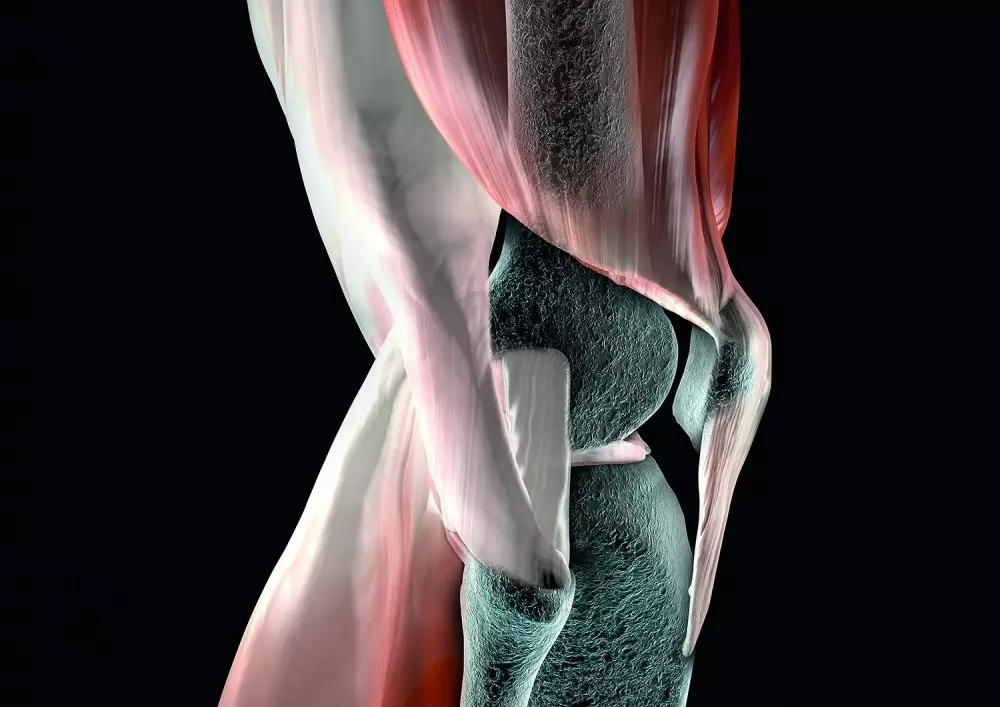

W dziale „Z praktyki gabinetu” znajdą Państwo tekst pt. „Metoda McKenziego w rwie kulszowej. Opis przypadku”. Bóle kręgosłupa dotyczą bardzo dużej części społeczeństwa, co może mieć źródło w siedzącym trybie życia i ograniczeniu aktywności ruchowej. Choć lekarze i fizjoterapeuci nieustannie poszukują nowych metod walki z bólem, do najpopularniejszych wciąż należy właśnie metoda McKenziego. Krzysztof Czupryniak przedstawia przypadek 32-letniej kobiety, spędzającej większość czasu w pozycji siedzącej, jednak uprawiającej przy tym jogging 3 razy w tygodniu. Opisuje badanie przedmiotowe oraz poszczególne sesje fizjoterapii z wykorzystaniem wspomnianej metody.